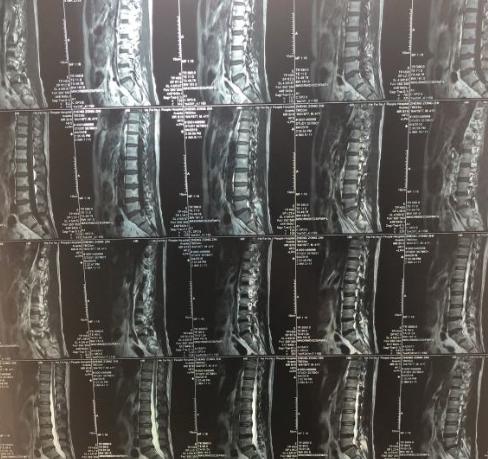

对于专业的医生,通过“视触动量”基本可以做到比较准确的“是否腰椎间盘突出”判断。所以如果出现了腰椎间盘异常,还是到正规医院寻求专业医生的建议比较有保障。